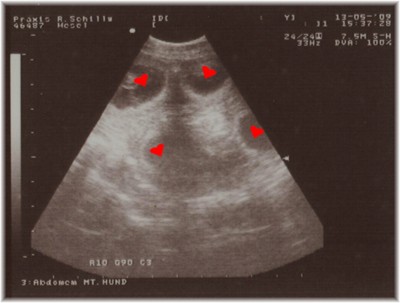

Vier der “Insassen” haben wir dann stellvertretend für alle

anderen K-chen auf Papier festhalten lassen:

Nichts gefunden? Hier dasselbe noch einmal mit einer kleinen Hilfestellung :-) !

Dicht aneinander gekuschelt haben diese vier kleinen Living Spots

und ihre weiteren Geschwisterchen nun noch bis ca. 16. Juni 2009 Zeit, ordentlich zu wachsen.